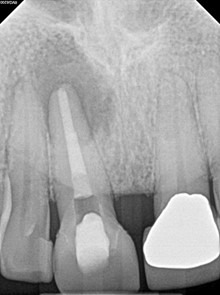

After one month, the patient returned for follow-up and the buccal sinus was still present. The tooth was re-accessed and the calcium hydroxide was replaced. At the two month mark, the buccal sinus tract was healed, but the canal still had continued mild drainage internally. A third round of calcium hydroxide was applied and left in place for 3 months. When the patient returned (5 months after initiating treatment), evidence of healing was observed radiographically around #7 and #8. RCT #8 was completed with an MTA obturation and RMGI orifice barrier. Sufficient ferrule and peripheral tooth structure was present and another post was considered not necessary.

Immediate Post-op (after long-term CaOH for 5 months)

6-month recall: Tooth #8 was asymptomatic and with no buccal sinus tract present. Tooth #7 remains responsive to cold testing. The patient had not returned to their GD for the permanent crown. The mobility in #8 was notably reduced and significant healing was observed radiographically. The lesion may heal with an apical scar, but apical surgery will likely not be necessary. The patient was scheduled for a 12-month recall and advised to return to their GD soon for the permanent crown.